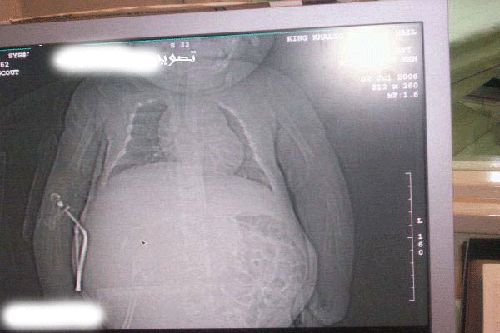

دختر باردار یکساله - عکس

دختر یک ساله ای در عربستان بار دار شده است دکتر معالج او گفته است این یک پدیده نادر در دنیا می باشد.

بر اساس تحقیقات پزشکی انجام شده نشان داده شده است زمانی که مادر او این دختر را حامله بوده دو تخمک در مادر وجود داشته که یکی در دیگری رشد کرده است این دلیل این است که تخمک دیگر درون دختر تازه به دنیا آمده رشد کرده است.

این دختر حامله نیست, بلکه جنین درون بدنش, جفت دو گلوش هست که داره توی بدنش به صورت انگلی رشد میکنه. من مانند این مسئله را دیدم. علت این مسئله این هست که مادر این کودک در ابتدا دو گلو حامله بوده ولی اشتباها یک جفت درون دیگری رشد کرده. دکترها باید با جراحی اون جنینو از بدن کودک در بیارند. |